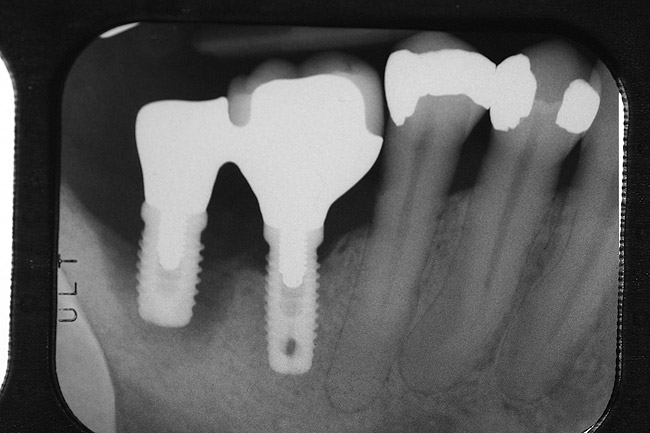

After complete management of moderate to severe periodontitis, including scaling and root planing and in some cases periodontal surgery, subsequent regular periodontal maintenance is reported to prevent tooth loss in up to 85% of patients over a long-term follow-up interval of up to 53 years.6,8 This high success rate of periodontal treatment is comparable to that of dental implants in replacing teeth lost to severe periodontal diseases, highlighting the predictability of maintaining the natural dentition in most patients with periodontal diseases9,10 (Figure 1A and Figure 1B).

Figure 1a  Long-term results of a case involving a 55-year-old woman treated by regenerative periodontal surgery followed by periodontal maintenance every 3 months for 8 years. (A) Radiograph taken in May 2000

Figure 1a

Figure 1b  Long-term results of a case involving a 55-year-old woman treated by regenerative periodontal surgery followed by periodontal maintenance every 3 months for 8 years. (B) radiograph of the same area taken in July 2008.</a></span><P>Figure 1b</P></div>    <div class=